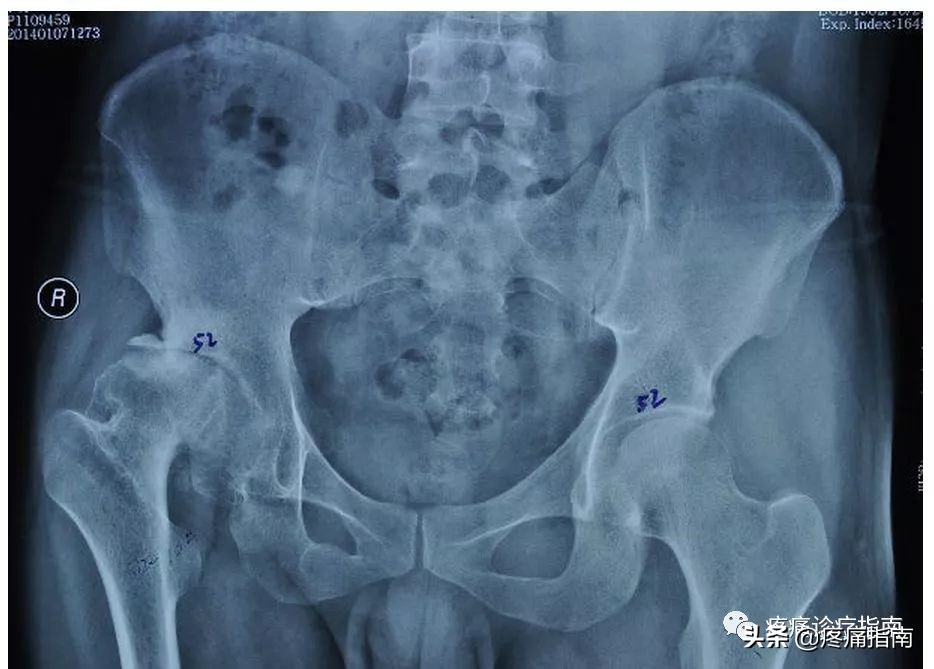

8.影像检查

X线摄片为骨性关节炎的常规检查,早期多正常,中晚期可见关节间隙不对称狭窄,关节面下骨硬化和变形,关节边缘骨赘形成及关节面下囊肿和关节腔游离体。根据Kellgren和Lawrecne的放射学诊断标准,骨性关节炎分为5级。0级正常。I级关节间隙可疑变窄,可能有骨赘。II级有明显的骨赘,关节间隙轻度变窄。III级中等量骨赘,关节间隙变窄较明确,软骨下骨质轻度硬化改变,范围较小。IV级大量骨赘形成,可波及软骨面,关节间隙明显变窄,硬化改变极为明显,关节肥大及明显畸形。

·骨性关节炎的诊断,需要根据病史、临床表现及影像学检查综合评价给予临床诊断。其中影像学检查是最为重要的依据。

③髋关节骨关节炎临床诊断标准:近1个月内大多数时间有髋关节疼痛;髋内旋≤15°;髋外旋>15°;血沉≤45mm/h;髋晨僵≤60min;血沉未做,髋屈曲<115°,年龄>50岁。满足①+②+④条,或①+②+⑤条或①+③+⑥+⑦条者,可诊断为髋关节骨关节炎。

④髋关节骨关节炎临床及放射学诊断标准:近1个月内大多数时间有髋关节疼痛;血沉≤20mm/h;X线片示股骨和 (或)髋臼有骨赘;X线片示髋关节间隙狭窄。满足①+②+③条,或①+②+④条或①+③+④条者,可诊断为髋关节骨关节炎。